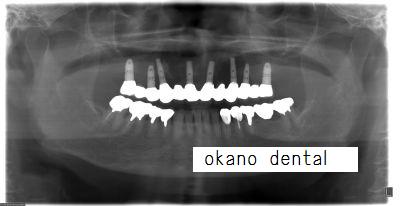

| A手術当日に仮歯のブリッジが入るオールオン6 (ノーベルバイオケア使用症例) |

| この症例の場合は、顎の骨の幅は、あまり広くはなかったですが 上顎洞までの距離があって13mmの長さのインプラントを選択することができたので 6本のインプラント(条件が整えばノーベルバイケアインプラント推奨)で行いました。 |

| これは、インプラントを入れた当日に仮の歯をブリッジにしていれた状態のレントゲンです。 インプラントを埋入するときのトルクが35N(ニュートン)から40Nの範囲で埋めることができないと その場で仮歯を入れて咬めるようにして帰っていただくこと(即時荷重)が出来ません。 骨がある程度硬くないと無理ですし、また、軟らかい骨でも削るのではなく押し広げるように形成することによって このトルクを作るようにします。 最初のドリルの感じで、どのように押し広げれば 適正なトルクで埋入することが出来るかがイメージ出来なければ無理です。 また、骨の幅がギリギリでシミュレーションとの誤差が0.3mm以内の精度でしかも方向を合わせなければいけません。 文字通り職人技です。 これが出来る歯科医師は、兵庫県でも極少数だと自負しております。 |